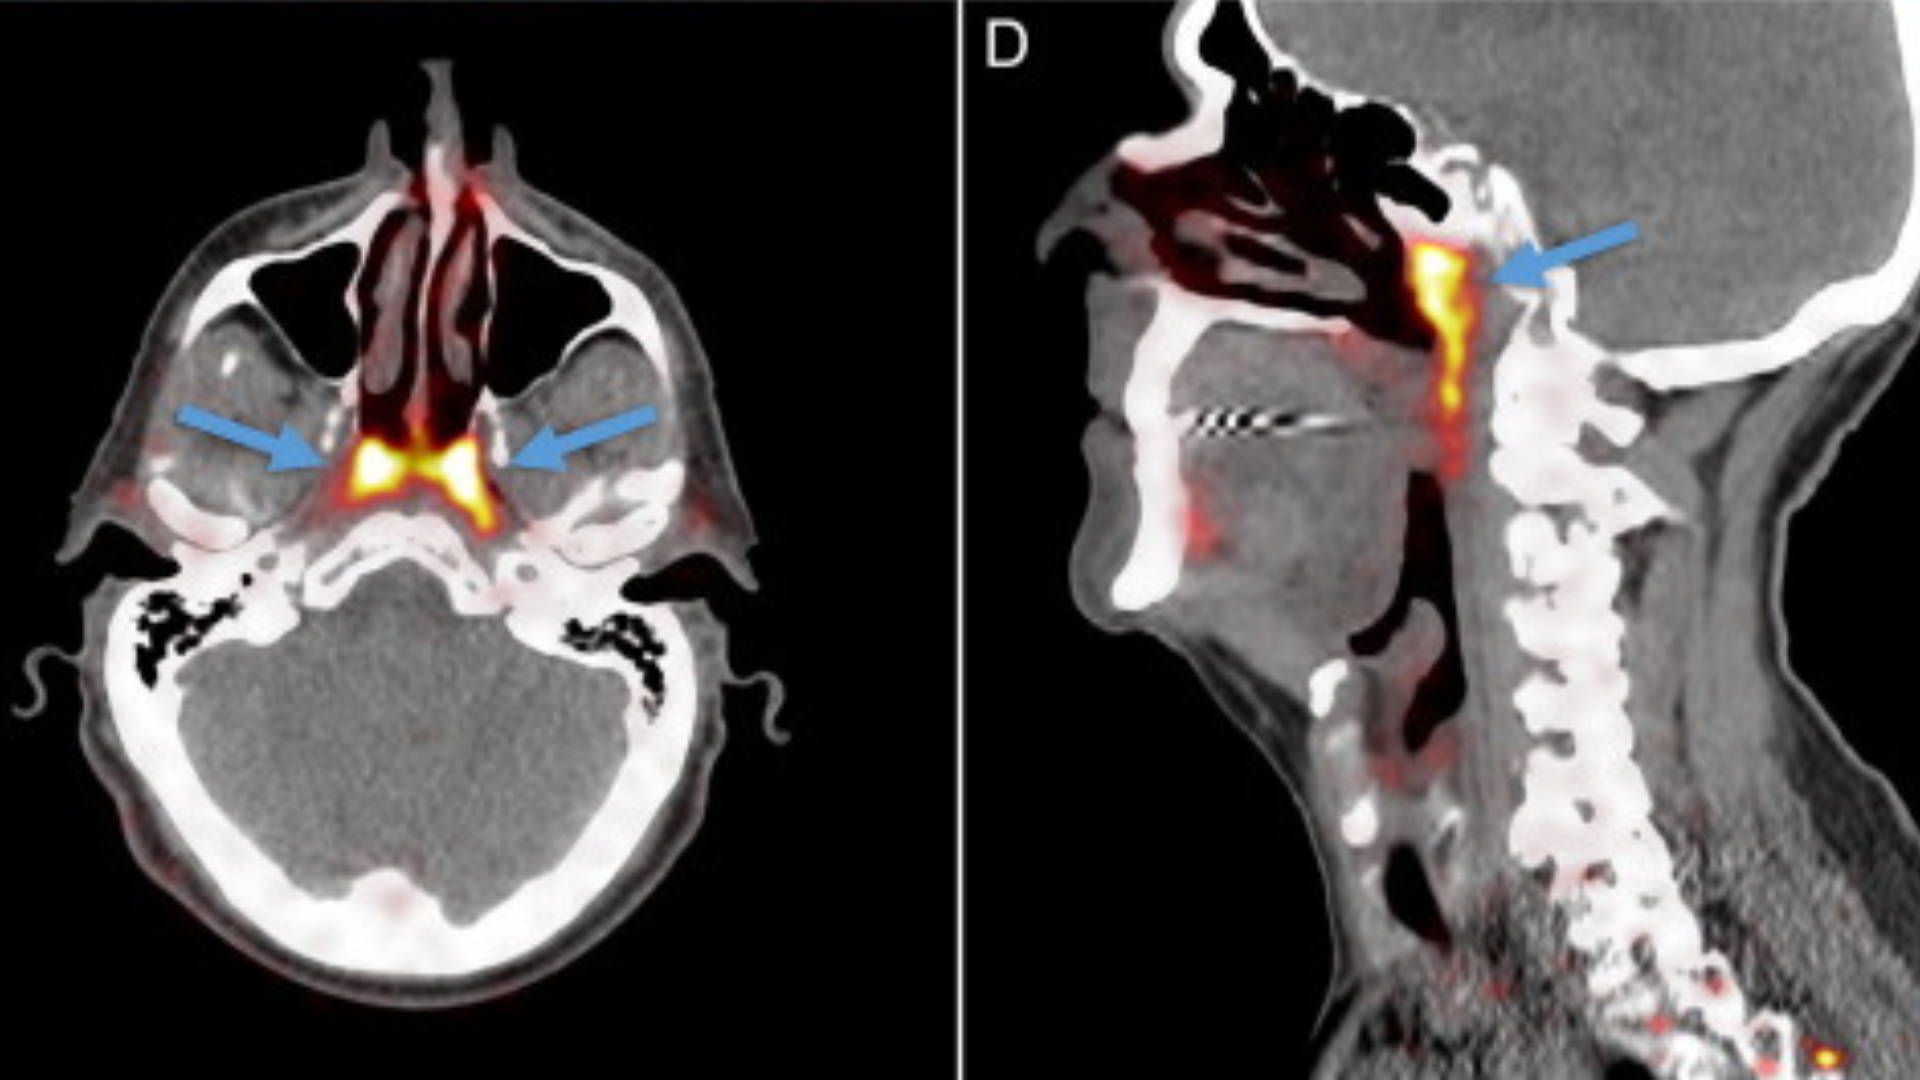

Onkológovia z Holandského onkologického inštitútu popri svojom výskume pacientov s rakovinou krku a hlavy použili takzvanú pozitrónovú emisnú tomografiu/počítačovú tomografiu so skenmi prostatických špecifických membránových antigénnych ligandov (PSMA PET/CT). Práve tie sa ukázali ako účinný spôsob sledovania šírenia rakoviny prostaty po tele.

Pred samotným skenovaním sa pacientom vstrekne rádioaktívna glukóza, ktorá pomôže zvýrazniť nádory u pacienta a doslova ich rozžiari.

Pri používaní tohto skenovania si onkológovia u pacientov všimli dve oblasti v hlave, ktoré sa na obrazovke nečakane rozsvietili. Rozhodli sa preto, že skenovaniu podrobia aj ďalších pacientov, u ktorých bol výsledok rovnaký. Aj u nich sa totižto rozsvietila presne tá istá oblasť.

Všetkých 100 naskenovaných pacientov malo malé svetlé škvrny. Podľa slov onkológov nešlo o žiadnu podivnú anomáliu, bol to, jednoducho, úplne nový orgán.

Nový objav, ktorý sa holandským onkológom podarilo učiniť, opísali aj v časopise Radiotherapy and Oncology. Ide o súbor slinných žliaz s viacerými drenážnymi kanálikmi, ktorý je umiestnený v zadnej časti nosohltanu.